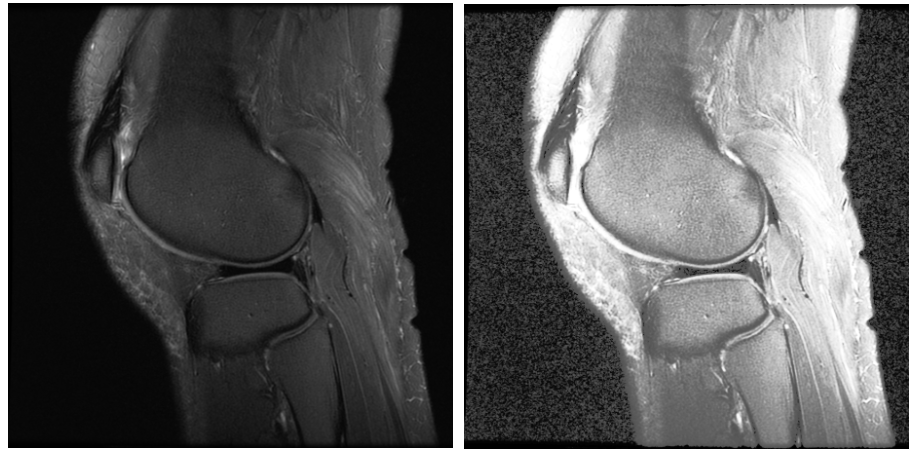

🌸CLAHE算法的应用:对于医学图像,特别是医学红外图像的增强效果非常明显:这篇博客做出了非常详细的讲解👉🏻CLAHE的实现和研究

这里放两张出自这篇博客的对比图感受一下: